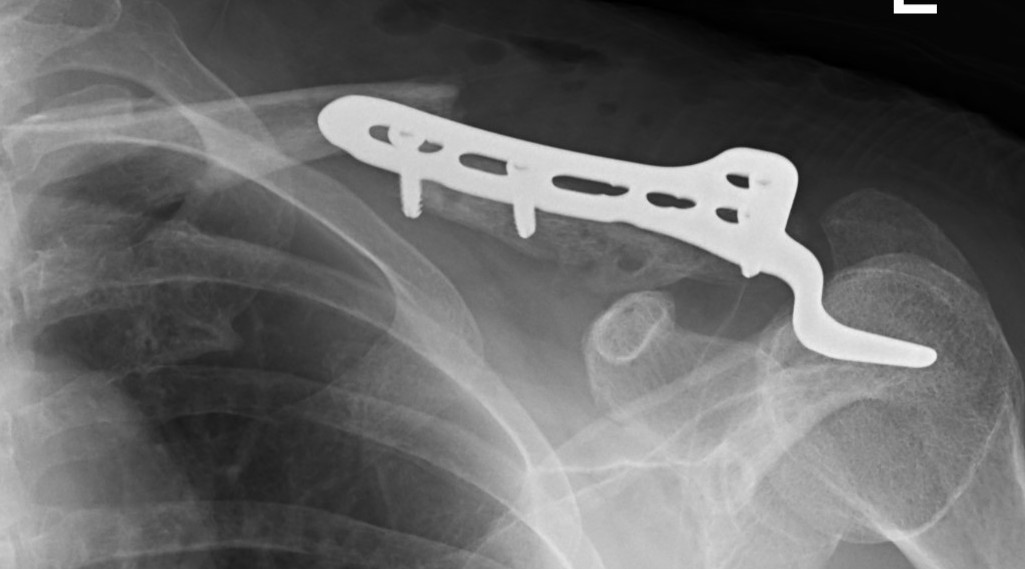

Hook Plate

Technique

Lazy beachchair

- tilt head away

- split delto-trapezius fascia to expose clavicle

- clean and reduce fracture

- detach trapezius from medial acromion to facilitate hook passage under acromion

- trial different hook depths +/- image intensifier

- avoid over-reduction / insufficient hook depth increases risk of acromial erosion

- 36 patients with displaced distal clavicle fractures treated with hook plate

- 95% union rate

- mean time to union 3 months

- hook plate removed in 92%

- 2 patients presented with late falls and fractures medial to the plate